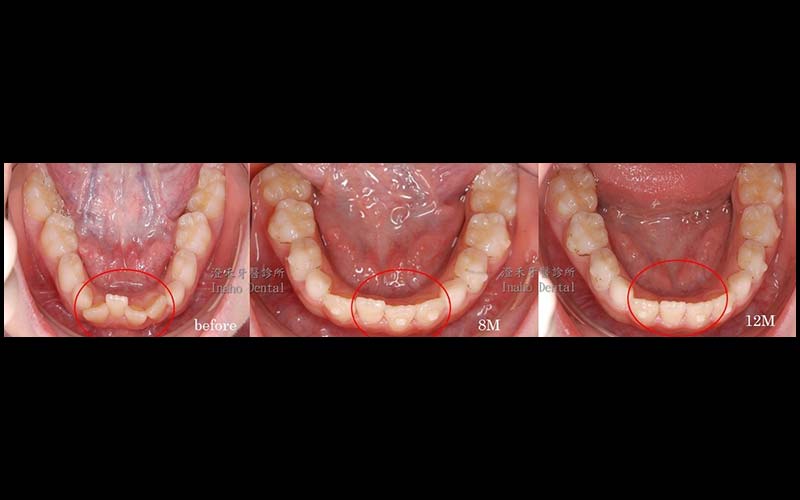

年齡:8歲

媽媽希望提早改善他牙齒凌亂不整齊,因門牙不易咀嚼食物,配戴了隱適美矯正器後,漸漸讓牙齒變整齊了,食慾也變好了。在黃金時期改善咬合不正,讓學童在生長發育的過程中可以更順利。

目前已矯正12個月